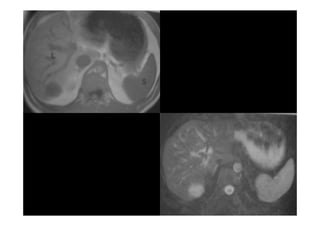

• O BAÇO MEDE ATÉ 15CM DE COMPRIMENTO,LOCALIZADO NO

O BAÇO MEDE ATÉ 15CM DE COMPRIMENTO,LOCALIZADO NO

QUADRANTE SUPERIOR ESQUERDO QUE SE APRESENTA COM

FORMATO ALONGADO.

• O CONTORNO DA BORDA SUPERIOR LATERAL É CONVEXO SE

O CONTORNO DA BORDA SUPERIOR LATERAL É CONVEXO SE

AMOLDANDO A PAREDE ABDOMINAL E AO CONTORNO DO

DIAFRAGMA.

• O HILO É ORIENTADO ANTERO MEDIALMENTE.

O HILO É ORIENTADO ANTERO MEDIALMENTE.

• A SUPERFÍCIE PÓSTERO

A SUPERFÍCIE PÓSTERO-

-MEDIAL DO BAÇO É CONCAVA ONDE SE

MEDIAL DO BAÇO É CONCAVA ONDE SE

AJUSTA AO FORMATO DO RIM ESQUERDO.

• A SUPERFÍCIE MEDIAL ANTERIOR AO HILO ENCONTRA

A SUPERFÍCIE MEDIAL ANTERIOR AO HILO ENCONTRA-

-SE EM

SE EM

CONTATO COM O ESTÔMAGO